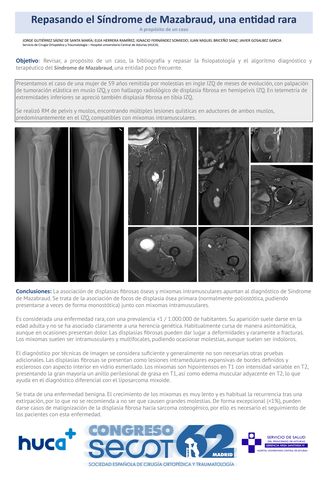

Repasando el Síndrome de Mazabraud, una entidad rara. A propósito de un caso.

JORGE GUTIÉRREZ SÁENZ DE SANTA MARÍA, ELEA HERRERA RAMÍREZ, IGNACIO FERNÁNDEZ SOMIEDO, JUAN MIGUEL BRICEÑO SANZ, JAVIER GOSALBEZ GARCIA